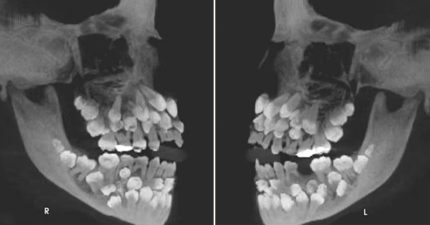

女童拔乳牙嚇壞牙醫!X光驚見「81顆牙塞滿嘴」